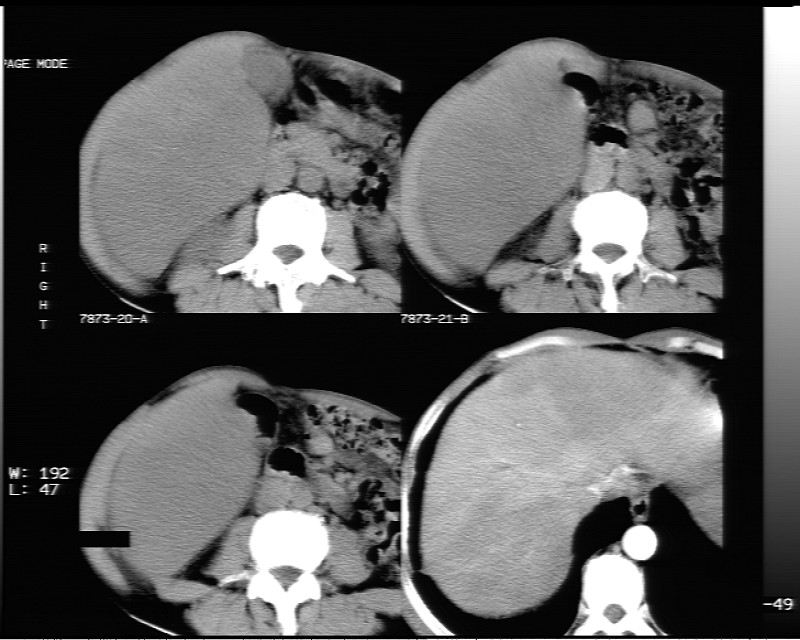

平扫示:

动态增强示:

支持脂肪肝【无占位性,高低密度区同期强化,平扫与强化的密度成比例】

不均匀性脂肪肝。肝脏体积稍大,不除外合并肝功能损害。

1.脂肪肝;

2.右肾结石。

不均匀性脂肪肝 。支持!右肾结石

1、不均匀脂肪肝;2、布加氏综合症(肝脏肿大,门脉纤细,下腔海绵状变性,肠系膜上静脉显著扩张)。